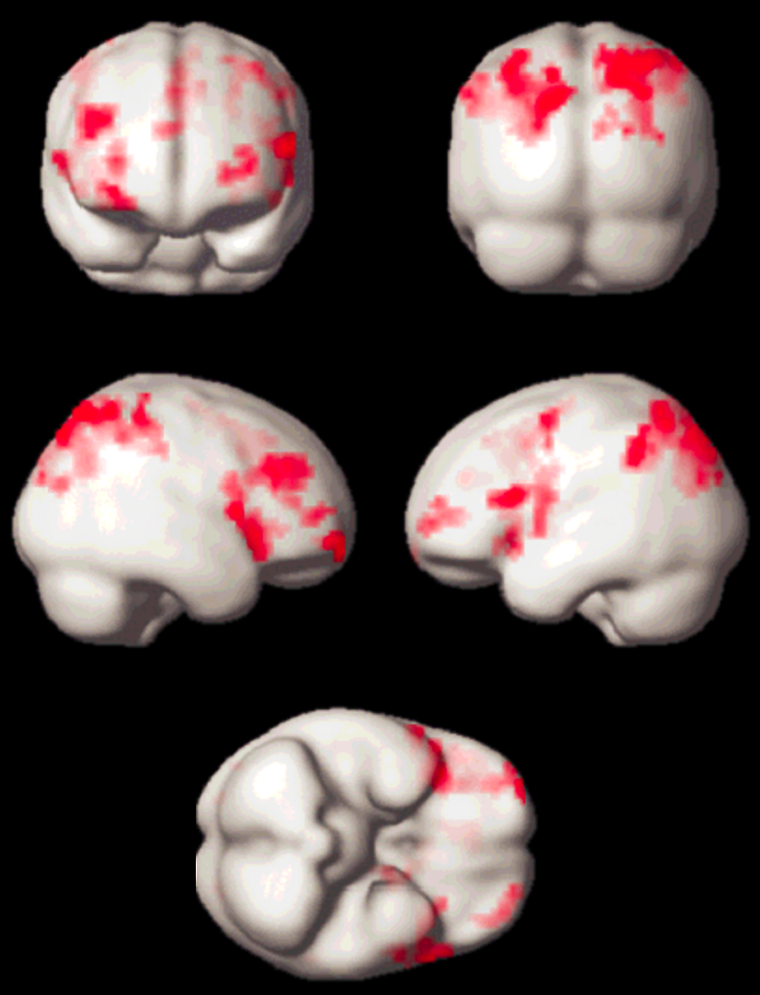

Meanwhile, quite a number of experi­ments have been performed, which led to new insights in neurocognitive research. Apart from activation in the primary vi­su­al cor­tex, activation of associated areas was demonstrated using a number of pa­ra­digms to test cognitive processing of motion, tex­ture, color, object re­cog­ni­tion, me­mo­ry, sound, and others (Figure 11-14).

Various para­digms using motor activation have been successfully examined. Numerous groups have in­ves­ti­ga­ted language processing us­ing a number of well esta­bli­shed pa­ra­­digms. In ad­di­tion to activation of the cere­bral cortex, the in­vol­ve­ment of the cerebel­lum in lear­ning tasks has been demon­strated. Sub­cor­ti­cal ac­ti­va­tion has been found, for example, in the nucleus genicu­latus (upon visual sti­mu­la­tion).

Figura 11-14:

Working memory test: typical activation pat­tern in the parietal cortex; cognitive / speech processing dor­­so­la­te­ral­ly.